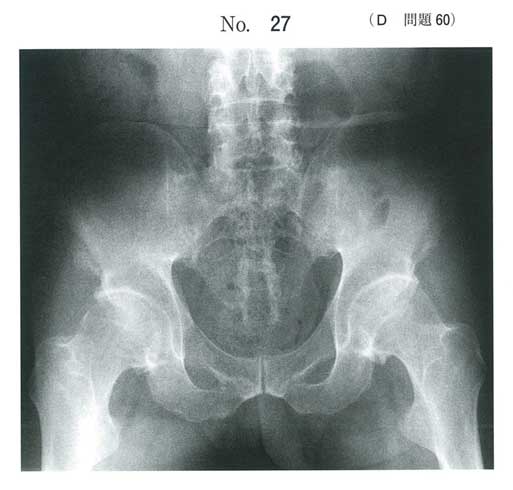

眼瞼結膜と眼球結膜とに異常を認めず、アキレス腱付着部炎からは強直性関節炎または反応性関節炎が疑われる(乾癬はない)

反応性関節炎は脊椎関節症、無菌性尿道炎、結膜炎の三主徴を特徴とするので考えにくい

E

運動で改善するはず

4: kotaro

e

強直性脊椎炎 bamboo spine 仙腸関節周囲も不鮮明か?

安静にしても軽くはならず、むしろ動くと改善するのがこの病気の特徴です。